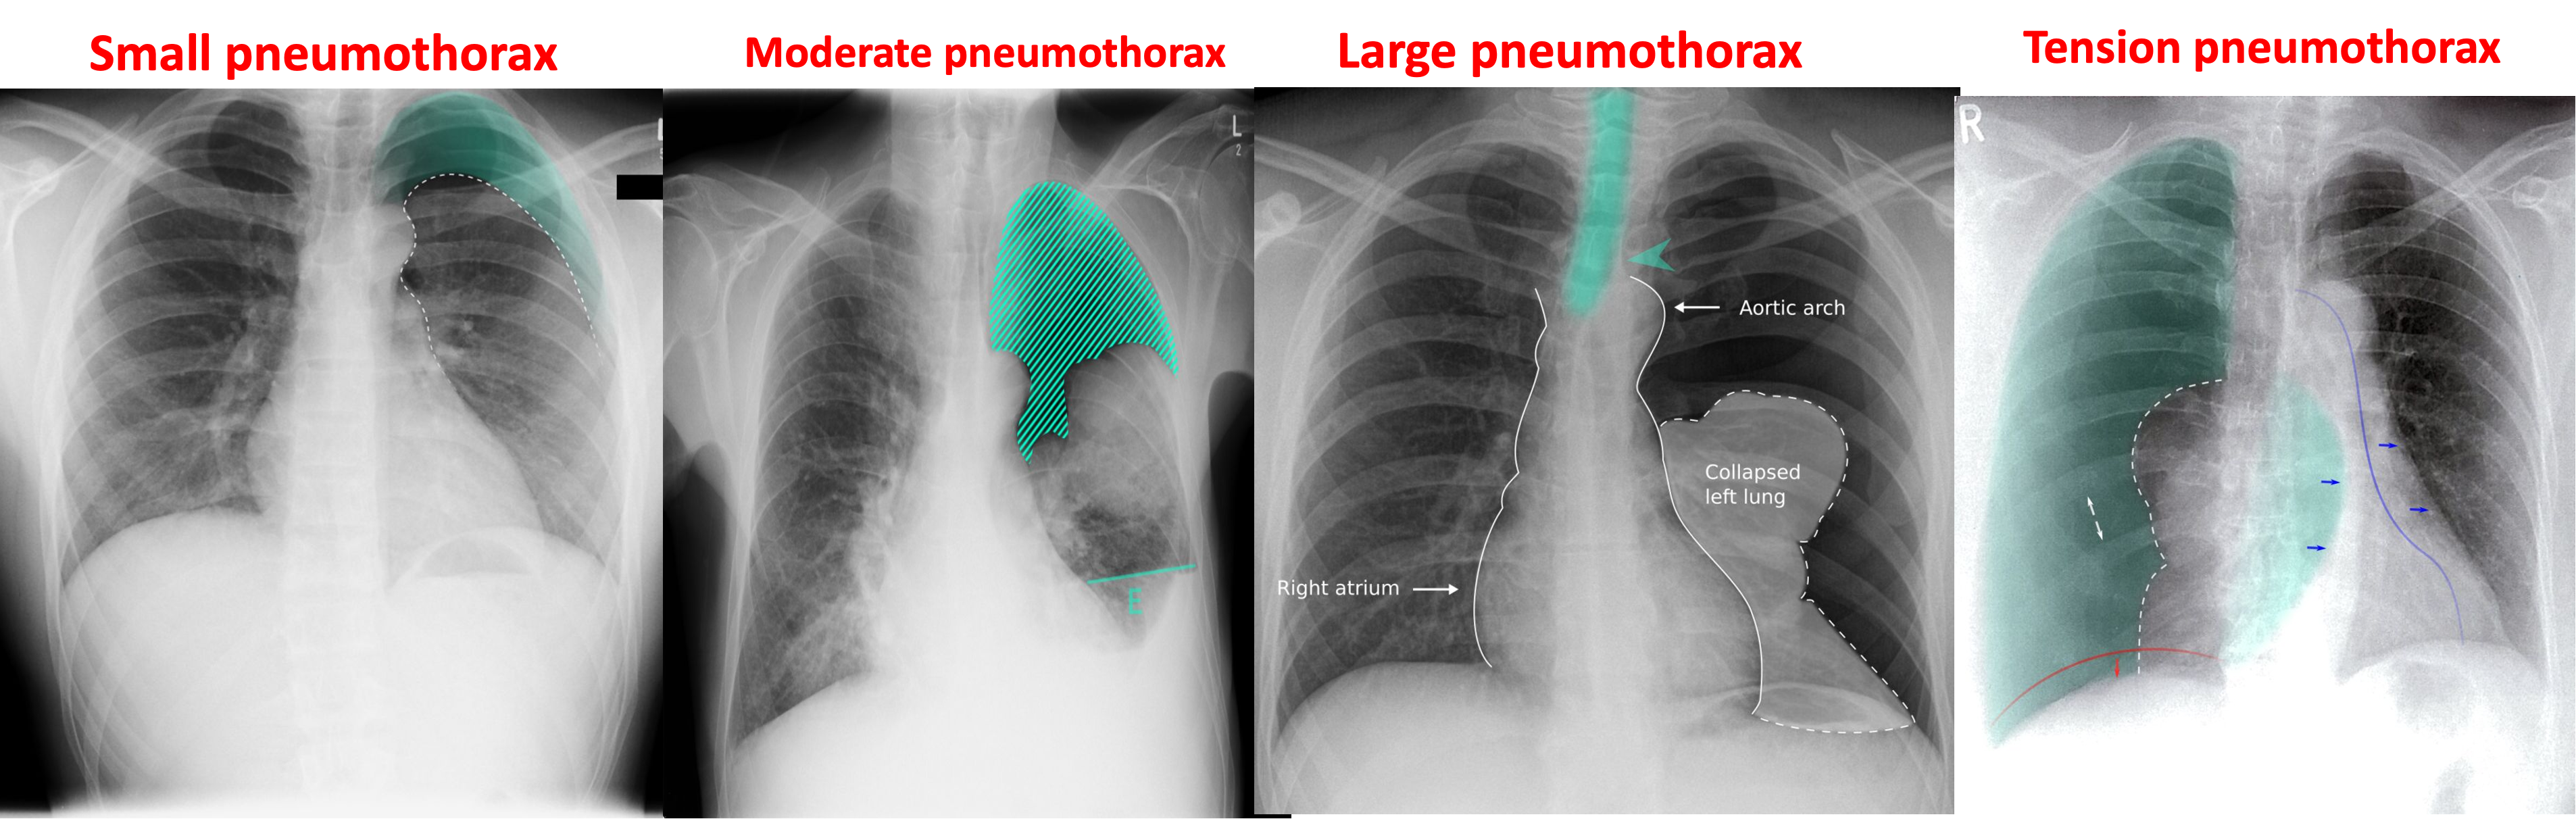

Small Pneumothorax:

< 20% of radiographic volume (best seen in expiratory film). Minimal symptoms.

Moderate Pneumothorax: When there is 20-50% of radiographic volume. Aspirate air.

Large Pneumothorax: When more than 50% of the radiographic volume and it causes shift of the trachea and mediastinum.

- Aspirate air.

Management of Tension Pneumothorax: Causes collapse of the lung and shifting of the trachea and mediastinum to the opposite side.